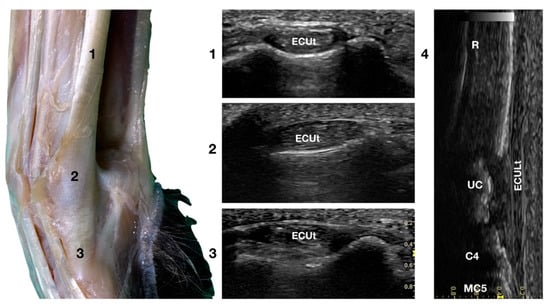

3.2. Lateral Carpal Face

Extensor Carpi Ulnaris Tendon Ultrasonographic Anatomy (ECUt)

The large Extensor Carpi Ulnaris tendon (ECUt), also known as Ulnaris Lateralis tendon was easily palpated and recognised as the most prominent structure on the lateral surface of the carpus (Figure 1b). When palpated, the tendon was firm in a standing patient, resembling a bony structure. This was due to the tendon fibrillar density and to the fact that the tendon ran in close contact with the underlying bony surface. At the ulnar notch level, the tendon was recognised in the transverse plane, as quite a flattened and relatively hypoechoic structure, rich in thin hyperechoic foci, and surrounded by a hyperechoic line (peritendineum) (Figure 5).

Figure 5.

Lateral carpal face centred on the Extensor Carpi Ulnaris tendon. At the ulnar notch level (2), the ECUt is seen as a wide and flattened oval tendon in direct contact with the osseous surface. Proximally (1), the tendon is thick and narrow. The ECUt runs on the lateral face of the carpus and ends at the base of the fifth metacarpal bone where it reaches its maximum width (3). On the longitudinal scan plane (4), the prominent fibrillar pattern of the large tendon is visible. The osseous surface beneath is recognisable. R, radius; RC, radiocarpal bone; C4, fourth carpal bone; MC5, fifth metacarpal bone.

In the larger patients, a multilayer onion-like appearance was rarely evident; the tendon was more uniform and homogeneous in the smaller patients. Proximally, reaching the tenomuscolar junction, which was located in the middle region of the antebrachium, the tendon was thicker and less wide. From its origin, the broad tendon passed laterally over the carpus, being held in place by a thin, transverse, tendinous band, which attached the ECUt to the accessory carpal bone. The tendon showed a prominent overall hyperechogenicity with a dense fibrillar pattern in the longitudinal scan. The ECULt ended laterally at the base of metacarpal V, and widened toward its insertion, achieving its maximum size. The standing position optimized the fibrillar pattern visualisation due to optimal alignment on the longitudinal scan. Carpometacarpal flexion and extension, and elevation of the fifth digit were used to check the tendon for adhesion or reduced range of motion. Medial and lateral stress was assessed to check for tendon compliance. The dynamic examination was easier to carry out when the paw was elevated.